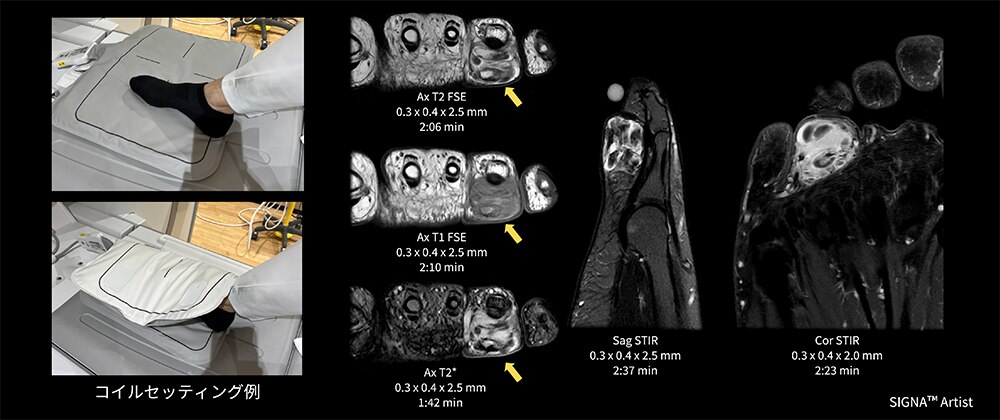

Case6 爪下腫瘤検査

10代の女性。半年前から第1足趾に痛みがあり足趾の爪甲部下に結節の出現と爪甲の変形がみられたためMRI検査を実施。結節サイズが8mmほどと小さかったので、MP Coilで足趾を挟むようにポジショニングを行った。

母趾末節骨足背内足部から足尖足背方向に突出構造あり、内部の骨髄様構造が末節骨構造と連続、軟骨帽様構造を認めることから、骨軟骨腫、外骨腫疑いとなった(図8)。

画像の様にコイルで挟むだけで足趾に合わせたFOVでの撮像が可能で、連続する骨髄の描出が出来た一例。

図8 爪下腫瘤検査におけるMP Coilのセッティング例と臨床画像